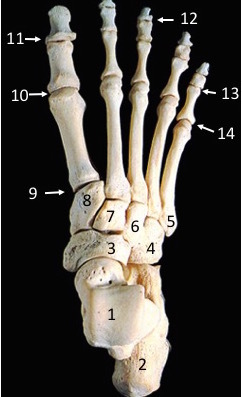

Tendon 4 belongs to which muscle?

Extensor hallucis longus

What innervates muscle 1?

Deep fibular nerve

Which muscle inserts on region 5?

Fibularis brevis

Which nerve innervates the skin in the region labelled 1?

Superficial fibular